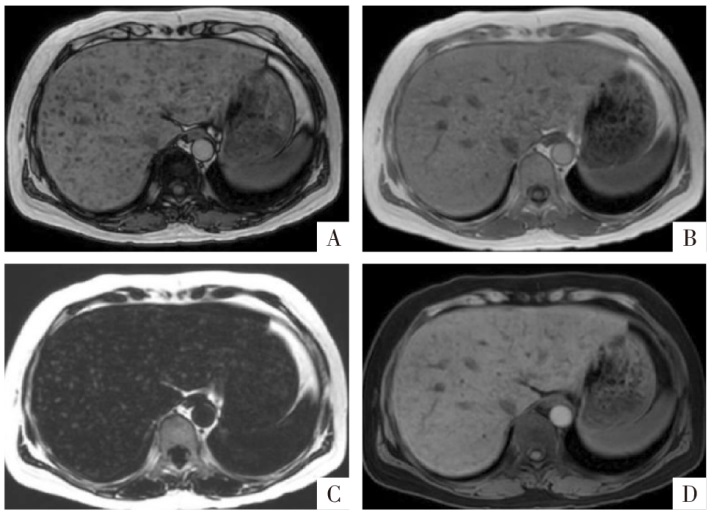

图2

脂肪变性MRI表现。病人男,67岁,肝细胞癌,病灶整体存在较严重的脂肪变性。A—D图分别为三维GRE序列T

1

WI同相位、反相位、水像(即脂肪抑制像)和PDFF图,病变在反相位(B)上整体信号较同相位(A)减低,水像(C)显示病灶信号减低程度较反相位弱。PDFF图(D)上相应病灶信号增高,PDFF约为16%。

图3

脂肪组织MRI表现。病人女,50岁,上皮样血管平滑肌脂肪瘤,病灶内含有小块的脂肪组织(粗、细箭头)。A、B、C图分别为三维GRE序列T

WI同相位、反相位、水像(即脂肪抑制像),显示相应脂肪组织在同相位(A)为高信号,反相位(B)中心为高信号,周边环形勾边,脂肪抑制像上病灶信号减低(C)。